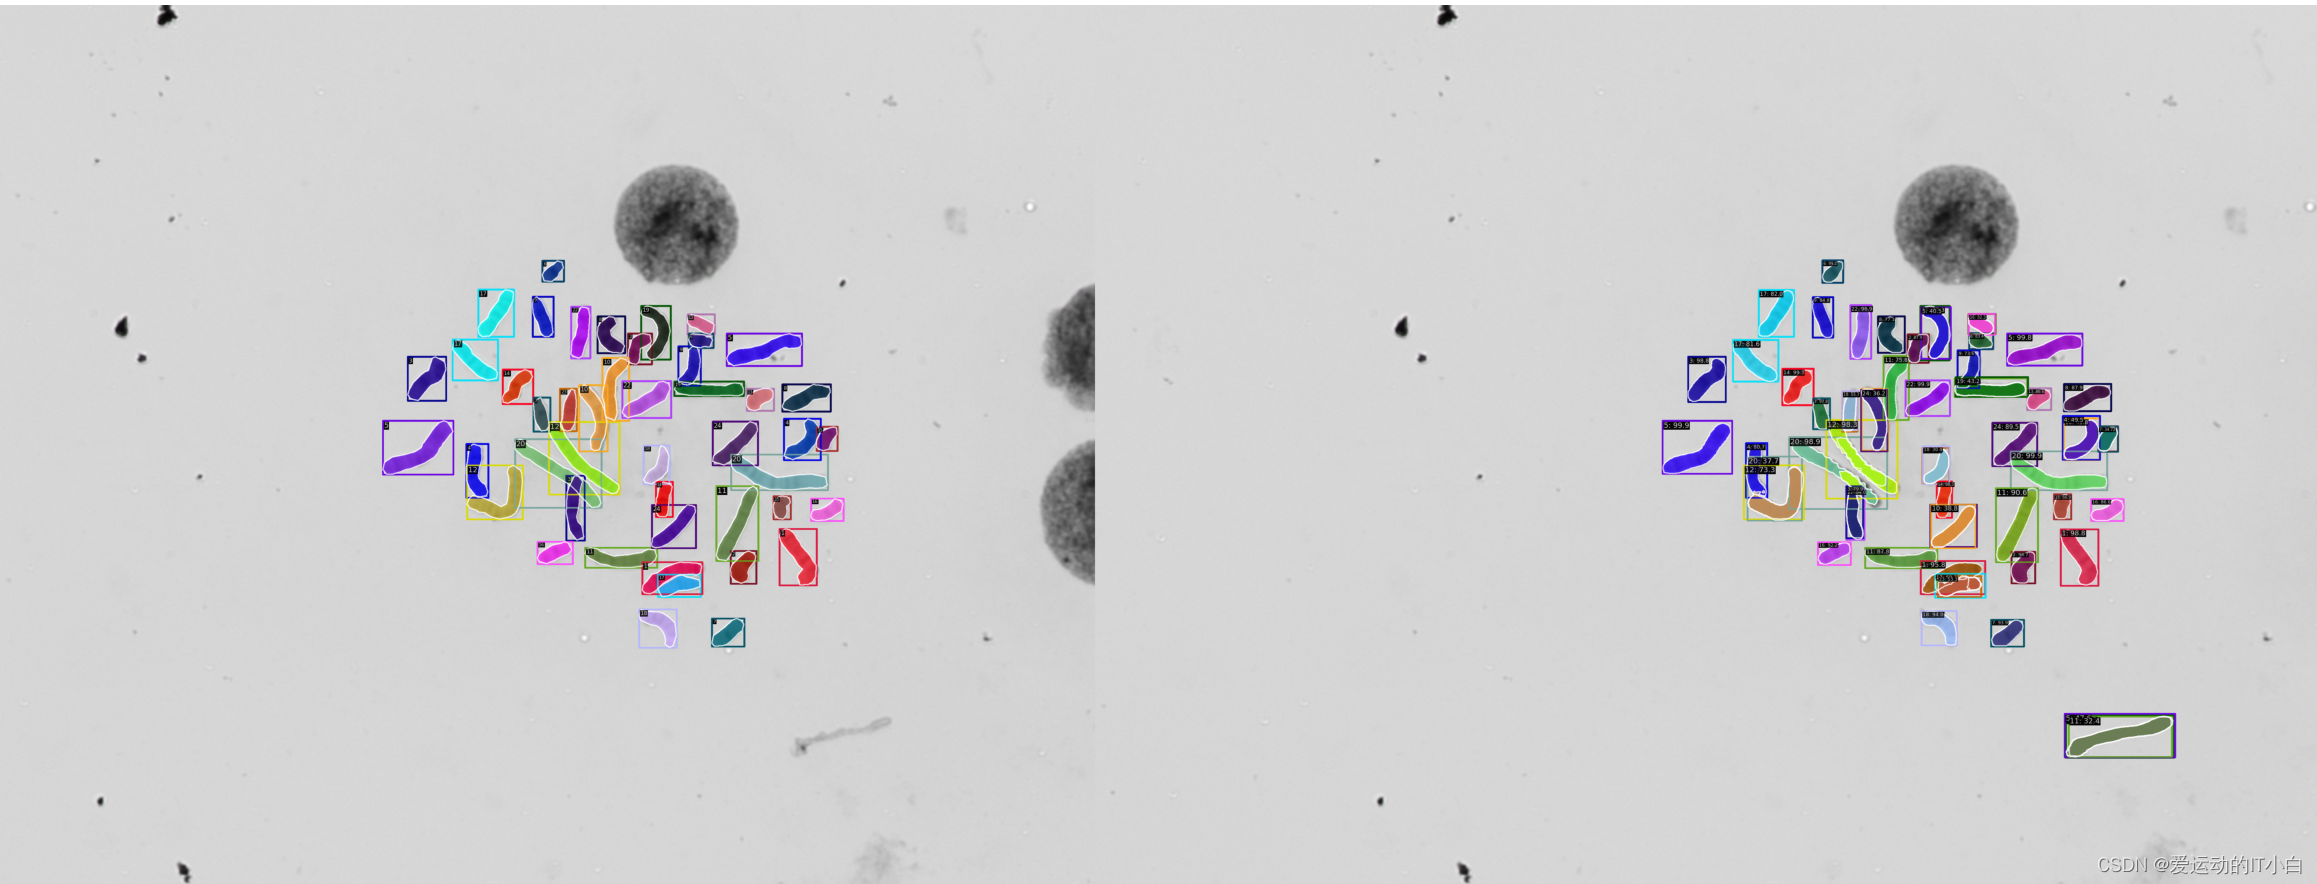

这篇文章将以maskrcnn为例,将labelme格式的数据转化为coco数据集,并展示染色体分类的训练测试过程

人体的染色体有24类,1-22号常染色体 23是x染色体 24是y染色体

可视化预览处理好的COCO数据集